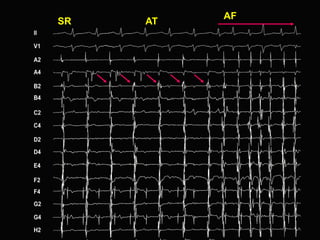

AF

SR   AT

C. Before Ablation   D. After Ablation

Surface ECG of repetitive nonsustained atrial tachycardia (AT)

originating from the right superior pulmonary vein (PV).